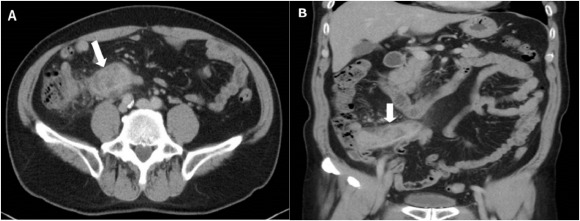

A 67-year-old man came to the outpatient department with intermittent right lower abdominal pain ongoing for 1 month. He denied any systemic disease and had no fever, chills, hematochezia, chronic diarrhea, nor body weight loss. Physical examination revealed right lower quadrant tenderness without rebound pain and muscle guarding. Positive psoas sign was noted. Blood tests were unremarkable except mild elevated C-reactive protein (4.9 mg/dL). Abdominal computed tomography (CT) demonstrated marked appendiceal wall swelling and intraluminal filling defect of contrast medium over the appendix (Figure 1). The colonoscopy revealed a protruding mass with edematous mucosa at cecum (Figure 2). Biopsy obtained at colonoscopy revealed inflammation of appendix mucosa. Due to the cancer could not be ruled out, a surgery with right hemicolectomy was performed and which showed a 7-cm length appendiceal tumor (Figure 3). Hematoxylin and eosin staining showed irregular glands with stromal invasion to muscularis propria, intraluminal mucin extravasation, and abscess formation were also seen (Figure 4A). Glandular arrangement lining by pseudostratified columnar cells with enlarged vesicular nuclei was noted under high magnification (Figure 4B). On the basis of these findings, he was diagnosed as colonic type adenocarcinoma of the appendix, T2N0M0, Stage I. After right hemicolectomy, he remains asymptomatic to date.

Computed tomography images: (A) cross section of abdominal computed tomography showed an appendiceal tumor (white arrow); and (B) marked appendiceal wall swelling and intraluminal filling defect of contrast medium over appendix noted (white arrow).